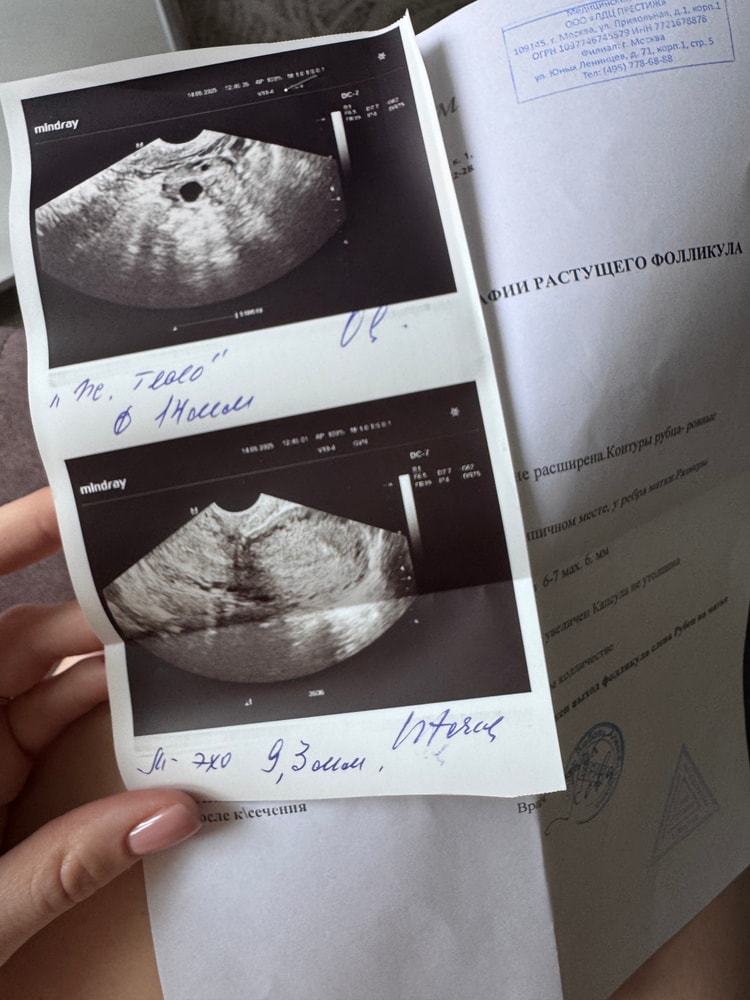

16дц - ДФ 23, симптомов нет, тест на О отрицательный

18дц - тест на О яркий, но уже отрицательный. Сильные боли стихли, но ост

Я очень расстроена, сходила еще раз на фолликулометрию (16дц) а мой фолликул еще не лопнул, уже 23мм. Врач говорит «такой хорошенький, как будто вот вот лопнет сего